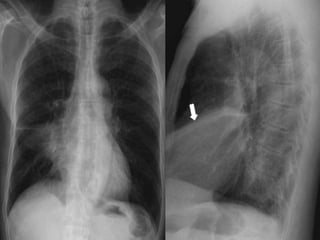

PA (right) and lateral (left) chest radiographs in a patient with tight left

lower lobe collapse. Note the triangular white opacity (black arrows)

behind the heart obscuring the posteromedial left hemidiaphragm.

Left lower lobe collapse.